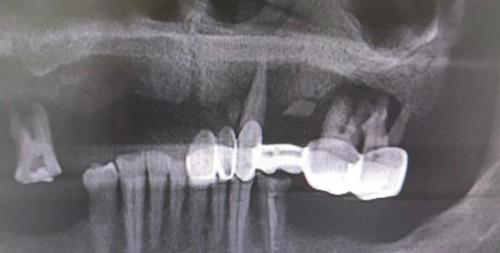

上半颌仅剩3颗残牙,咀嚼功能几乎没有

做了活动假牙之后,金先生总感觉口内不舒适,每天都要摘取下来清洗,给生活带来极大的不便。金先生动了做种植牙的念头,可是他的心血管有大面积堵塞,长期在服用抗凝血的药,咨询了很多口腔医生都无法解决。而且金先生牙槽骨萎缩十分严重,无法进行常规种植。

6颗种植体恢复上半口14颗牙齿

黎强博士当天为金先生做种植手术,种下6颗种植体恢复上半口14颗牙齿,当天就戴好牙齿可以吃饭了,这一趟萧山之行,让金先生和爱人都感到非常开心。